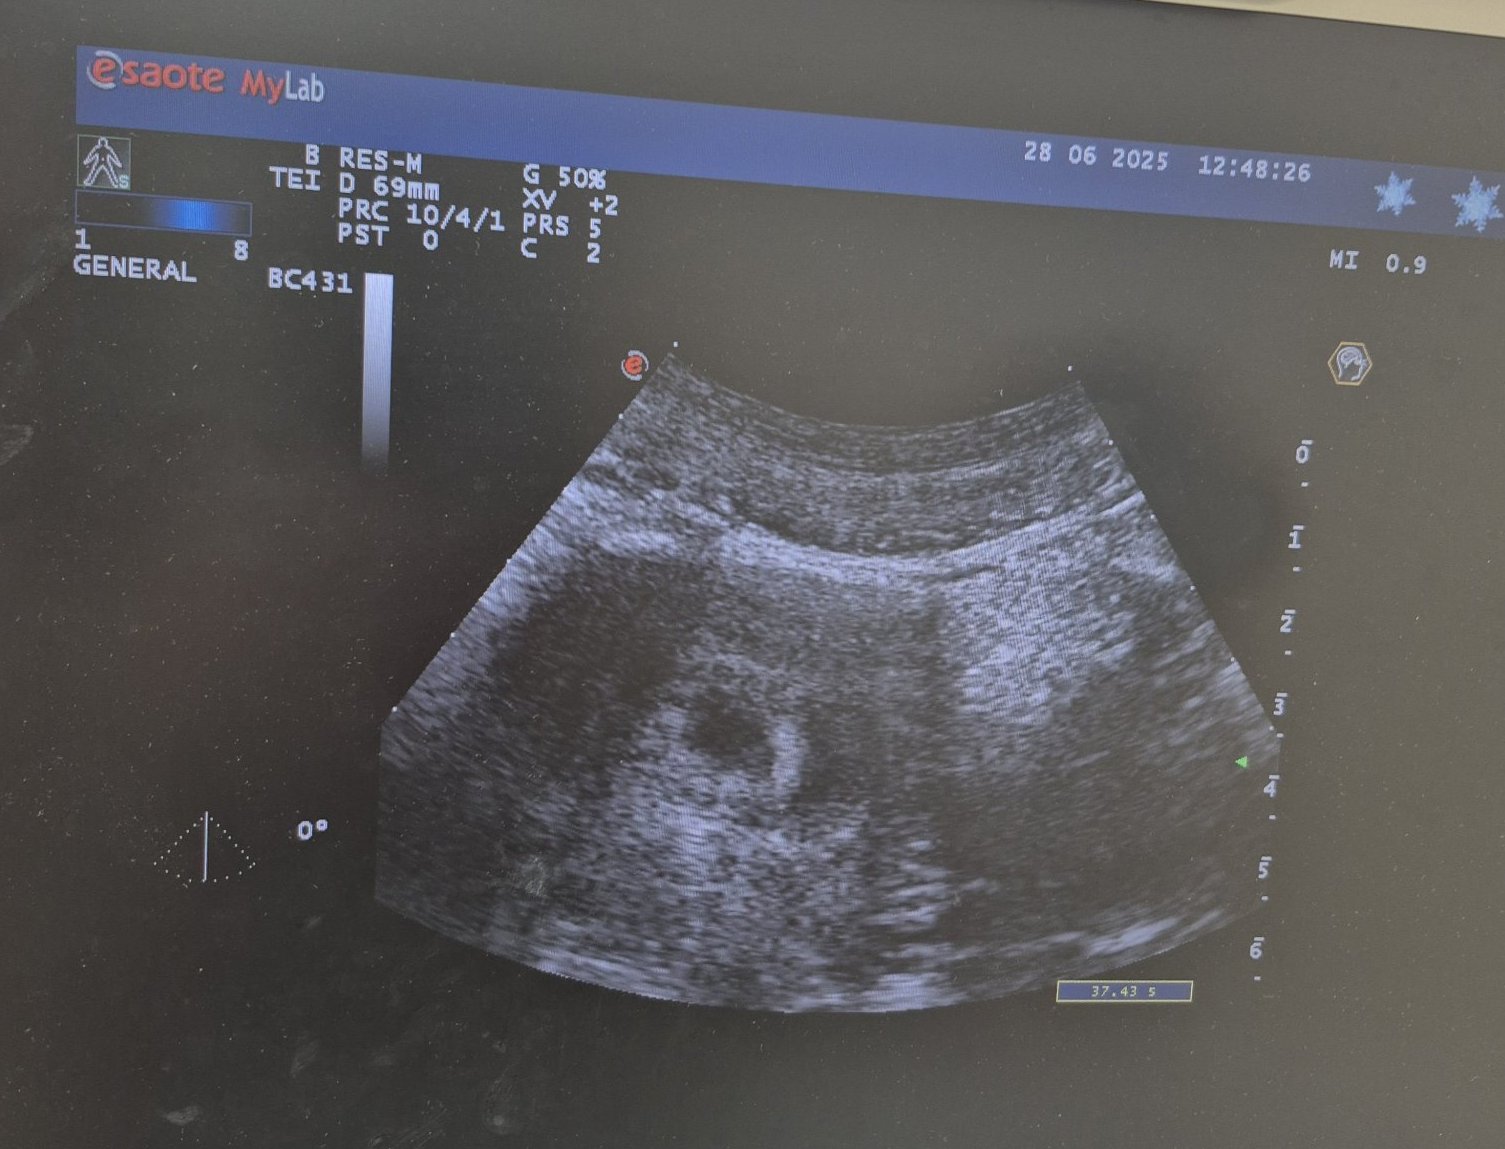

Stubbornh,как са я потвърдили? На снимката няма ясно изразен сак,нито има отбелязана гестационна седмица.

Има измерено нещо ,но не е уточнено дали е размер на матката,сак или друго.

Ами точката (сак) се вижда, даже с малко фантазия се вижда ембрион вътре, но изглежда снимката не е правена с много модерна техника. Щом са и потвърдили, значи са сигурни в това, което виждат. Лекарят е огледал и видял повече от това, което ние виждаме на тази снимка Simple Smile по-добре да му се довери и да не се притеснява според мен. Засега е видяно каквото трябва, така че всичко е наред. Всички имаме натрапчиви негативни мисли в началото, гледайте да ги прогонвате, доколкото можете Hug така е най-добре и за вас, и за бебето Blush

-Sunshine-,въпросът ми беше насочен конкретно към Stubbornh ,а не към някой друг. Не претендирам,че съм компетентна, но на направеното ехографско изследване не се вижда гестационна сак, нито е посочена гестационна възраст. Именно поради тази причина се питам на какво основание лекарят е стигнал до съответния извод. Ако е направен кръвен тест за ЧХГ и той е бил положителен,това би обяснило нещата. Но при липсата на такава информация остават неясноти, които ми се струва редно да бъдат изяснени.

На мен, честно казано не ми се вижда наред. За тази висока стойност, която има Stubbornh, трябва да се види и сак, и ембрион. А аз виждам само нещо като сак, дано греша и наистина всичко е наред, както казва Sunshine.

Защото това не е снимка на матка, а на десен яйчник и жълто тяло. Опитах се да обясня одеве, но Sunshine ми докладва коментарите и биват изтривани. Няма как да има ембрион или гестационен сак в жълто тяло! Предполагам, че има и друга снимка от УЗ или следствие на големината на жълтото тяло и лигавицата е направено предположение.

Защото това не е снимка на матка, а на десен яйчник и жълто тяло. Опитах се да обясня одеве, но Sunshine ми докладва коментарите и биват изтривани. Няма как да има ембрион или гестационен сак в жълто тяло! Предполагам, че има и друга снимка от УЗ или връз основа на големината на жълтото тяло и лигавицата е направено предположение.

Може би жената е объркала снимката.

Никой нищо не оспорва просто, заради снимката стана доста странно.